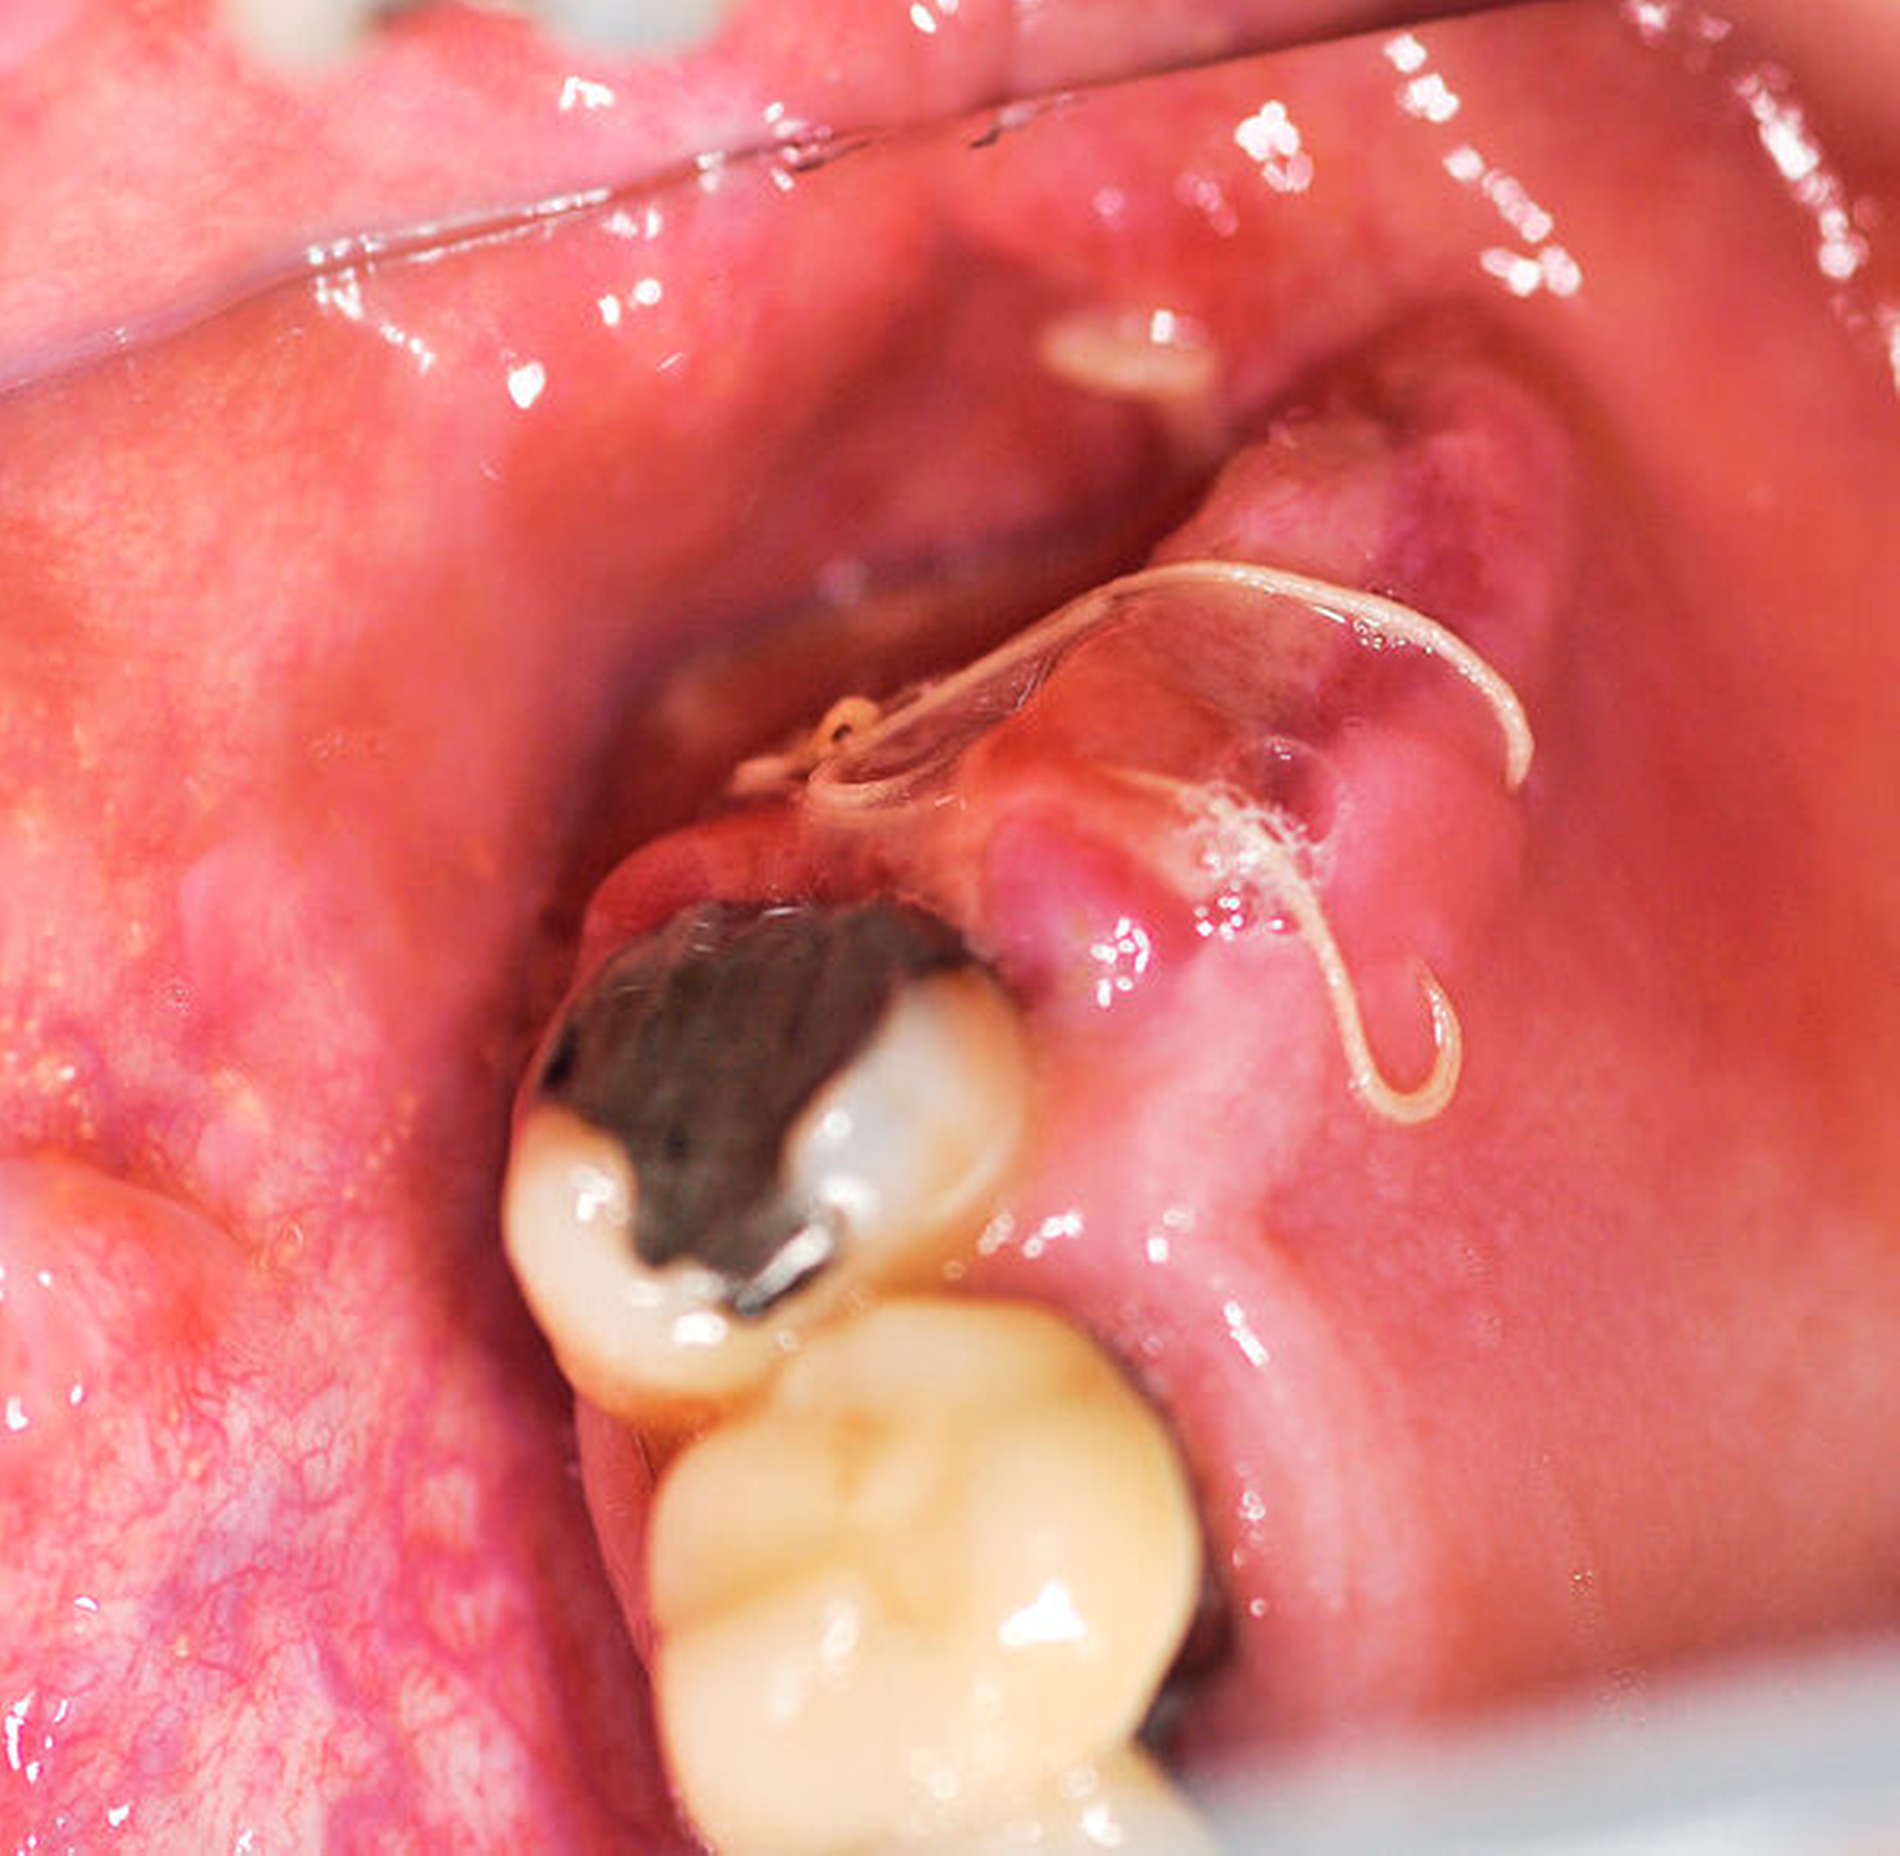

Ein 50-jähriger Patient ohne Nebenerkrankungen und Medikation stellte sich auf Überweisung seines Hauszahnarztes mit einem unklaren, tumorähnlichen Befund im rechten Oberkiefer vor. Intraoral zeigte sich vor allem distal des Zahns 17 eine fibrinbelegte, ulzerierend erscheinende Läsion. Die Zähne 17 und 16 reagierten negativ auf eine Vitalitätsprobe und wiesen einen Lockerungsgrad von I bis II auf. Insbesondere der Zahn 17 war mit seiner partiell freiliegenden Wurzeloberfläche auffällig (Abbildung 1). Eine Panoramaschichtaufnahme erbrachte den Nachweis einer starken Elongation des oberen, rechten zweiten Molaren mit erweiterten Parodontalspalt (Abbildung 2).

Eine laborchemische Auswertung des Blutes ergab keine Auffälligkeiten. Unter der Verdachtsdiagnose eines odontogenen Tumors mit der Differenzialdiagnose eines Malignoms wurde eine Biopsie durchgeführt und ein ulzerierendes peripheres Riesenzellgranulom der Gingiva ohne Anhalt von Malignität diagnostiziert.

Bei der anschließend durchgeführten Resektion im Oberkiefer wurde der Befund in toto mit den Zähnen 17 und 16 bei Einhaltung eines geringen Sicherheitsabstands unter Eröffnung der Kieferhöhle exzidiert. Der entstandene Defekt wurde mithilfe eines gestielten Mukoperiostlappens unter Einbezug des Bichatschen Fettpfropfs gedeckt.

Die pathohistologische Untersuchung des entnommenen Präparats ergab zahlreiche zentrale Riesenzellen in einem gefäßreichen mesenchymalen Stroma und bestätigte somit die initiale Diagnose. Die lokale Wundheilung gestaltete sich komplikationslos (Abbildung 5).